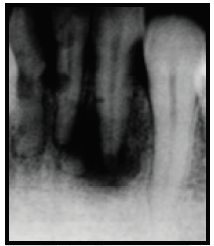

Analise a figura a seguir:

Radiograficamente, pode-se visualizar: